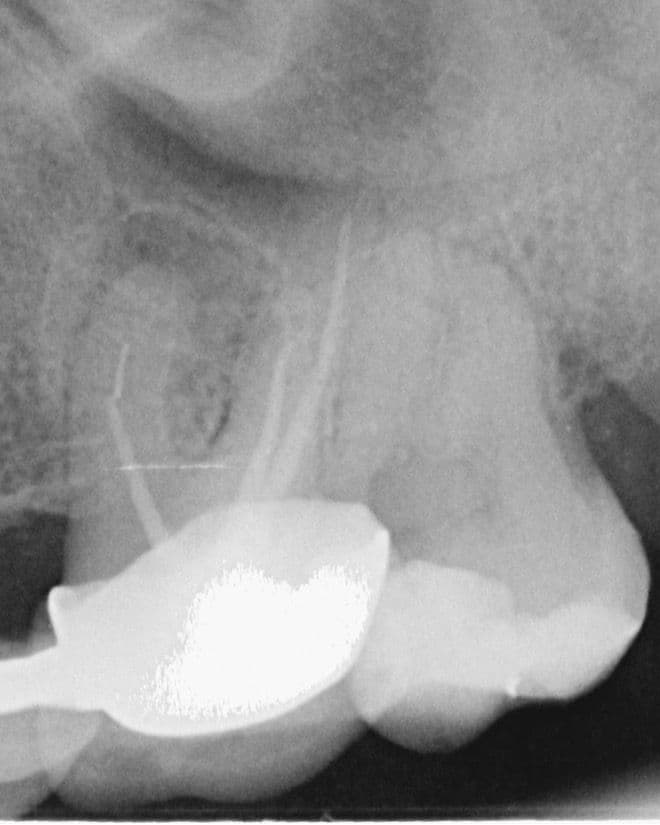

45 yaşında sağlıklı kadın hasta, 2023 Mayıs ayında protetik gereksinimden dolayı prepare edilen 26 numaralı dişinde işlem sonrası gelişen şiddetli ağrı şikayeti ile kliniğimize başvurdu İlgili dişe kök kanal tedavisi işlemi planlandı (Şekil 1).

(Şekil 1) 2023 Mayıs 26 No Pre-Op radyografi.